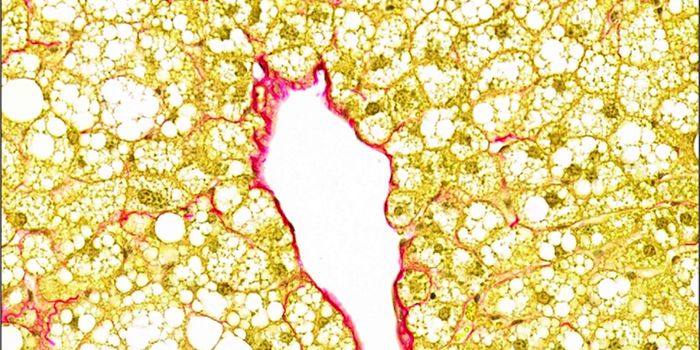

FEB 15, 2023Health & MedicineSeveral studies have shed new light on nonalcoholic fatty liver disease (NAFLD), a shockingly common disorder that is th ...